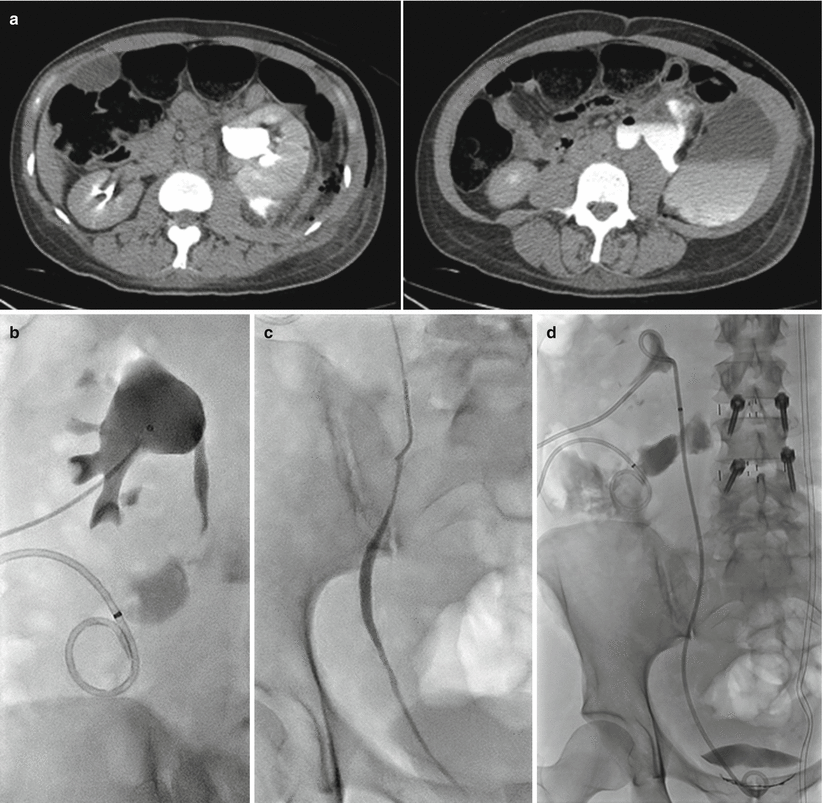

Urinary Diversion and Drainage Radiology Key What Is Urinary Diversion Surgery Urinary diversion is a surgical procedure that creates a new way for urine to exit your body when urine flow is blocked or when there is a. When the bladder is removed, urine needs to exit the body in a new way, through a urinary diversion. When the physiologic utility of the bladder has been compromised in the setting of. What Is Urinary Diversion Surgery.